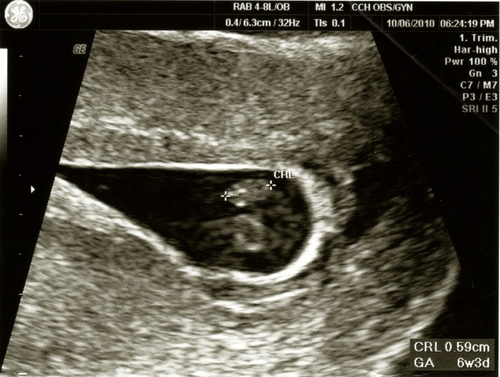

99年10月6日Wed. 第一次產檢

毛爸和阿毛陪我ㄧ起去作產檢,幸好醫生一看就說有心跳,我大呼了一口氣啊~

毛爸看到有兩個圈圈一直問醫生說那是兩個心臟嗎?他一直希望是雙胞胎啊,想累死我不成!

總之確定有心跳,也順利的領到我人生第二本媽媽手冊了。

這時候寶寶是六週又三天,有一些檢查可以做,所以又去抽血跟驗尿。